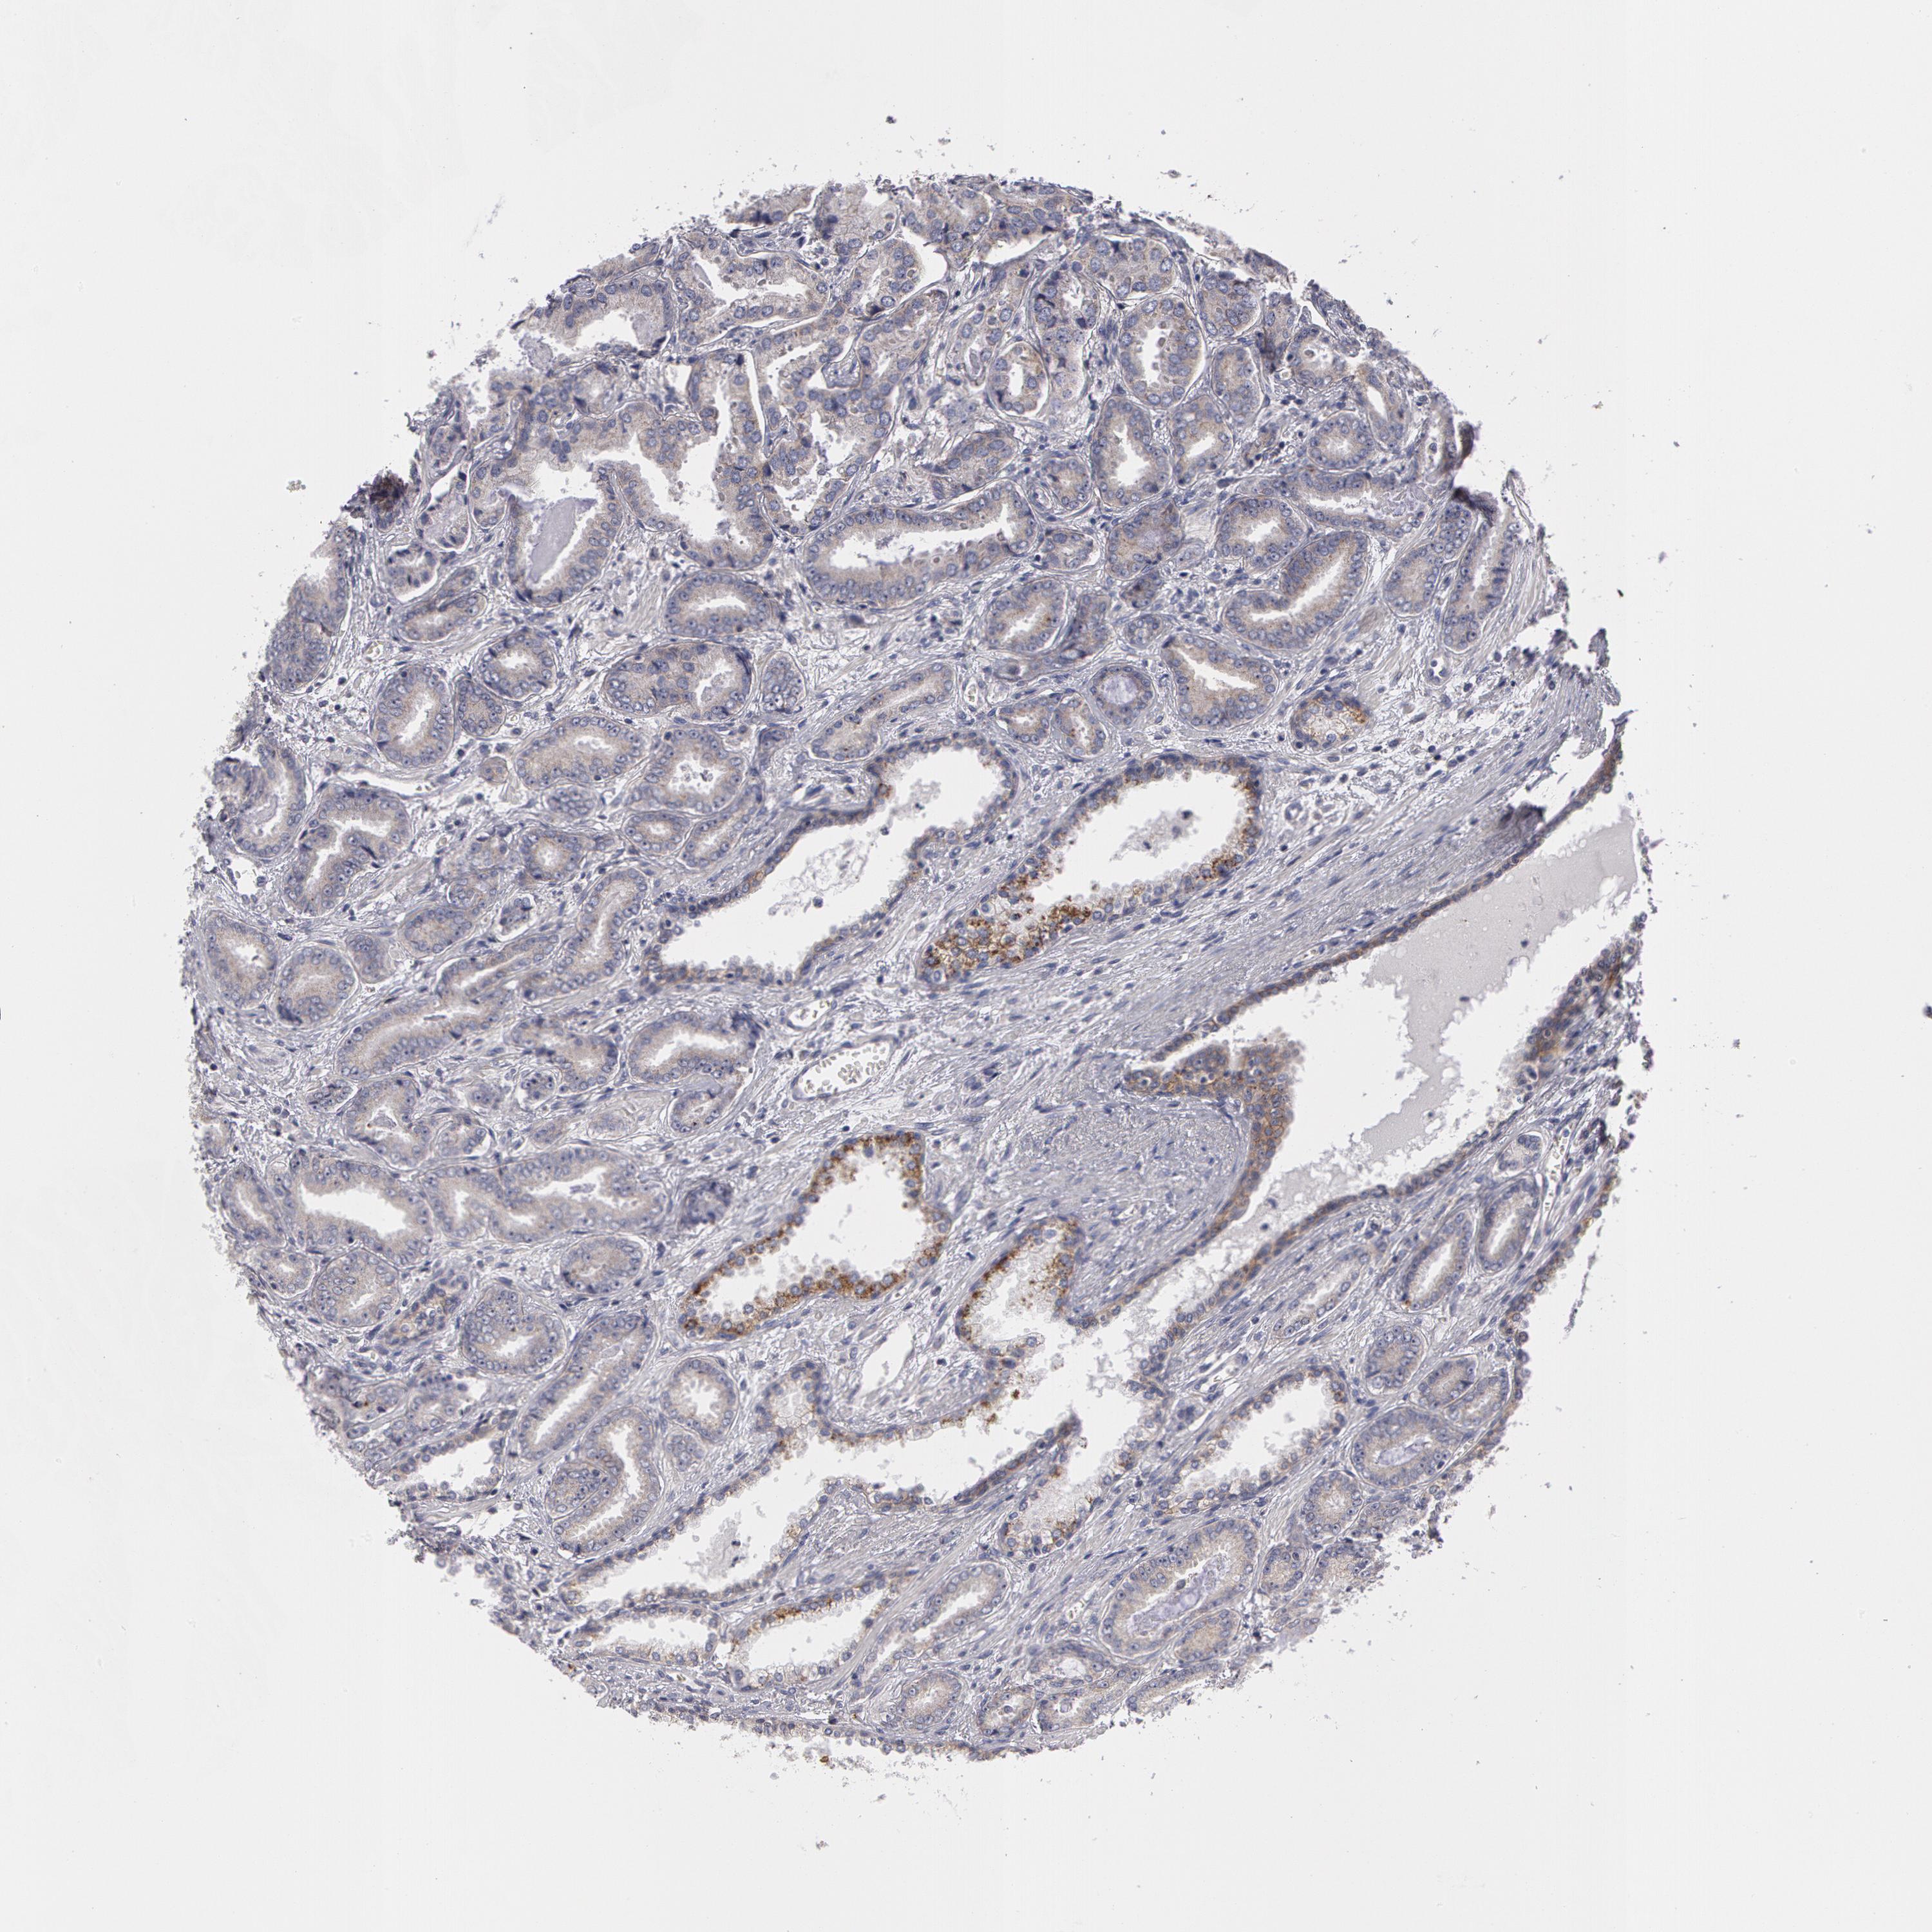

PROSTATE CANCER - Protein expressioni

A mouse-over function shows sample information and annotation data. Click on an image to view it in a full screen mode. Samples can be filtered based on level of antibody staining by selecting one or several of the following categories: high, medium, low and not detected. The assay and annotation is described here.

Note that samples used for immunohistochemistry by the Human Protein Atlas do not correspond to samples in the TCGA dataset.

Antibody stainingi

Antibody staining in the annotated cell types in the current human tissue is reported as not detected, low, medium, or high, based on conventional immunohistochemistry profiling in selected tissues. This score is based on the combination of the staining intensity and fraction of stained cells.

Each image is clickable and will lead to virtual microscopy that enables deeper exploration of all samples and also displays staining intensity scores, fraction scores and subcellular localization as well as patient and tissue information for each sample.

Antibody HPA001383

Antibody CAB000043

Antibody CAB020416

Antibody CAB062555

Staining

High

Medium

Low

Not detected

Intensity

Strong

Moderate

Weak

Negative

Quantity

>75%

75%-25%

<25%

None

Location

Nuclear

Cytoplasmic/membranous

Cytoplasmic/membranous,nuclear

Adenocarcinoma, Medium grade

Adenocarcinoma, Low grade

Adenocarcinoma, High grade

Adenocarcinoma, NOS